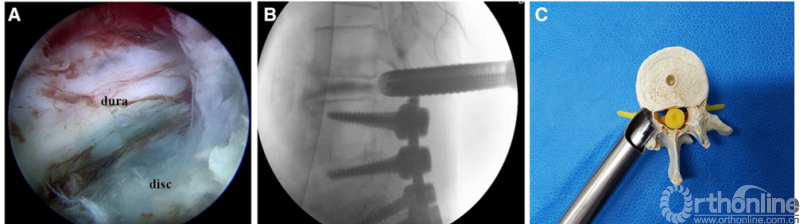

为了更好地监视内镜下减压及融合过程,减少并发症的发生。2017年Youn等报道了全内镜下腰椎减压融合技术(Full endoscopic lumbar interbody fusion ,FELIF),该技术与之前技术相比,优势在于铰刀和Cage置入椎间隙的过程也在内镜监视下进行,从而可以有效避免相关神经损伤和融合器位置不佳的问题。

2017年Heo等报道了双通道下全内镜腰椎减压融合技术,该技术与Youn等所报道的技术有所不同,每个融合节段需要建立两个工作通道,一个通道用于操作,另一个通道放置内镜,整个操作过程类似于关节镜下操作,该技术的手术适应症比较广泛,包括退行性腰椎滑脱、先天性腰椎滑脱、腰椎管狭窄症合并腰椎不稳、中央管狭窄同时合并椎间孔狭窄者,能够治疗的节段包括L3/4到L5/S1。结果显示该技术效果良好,并且无神经相关并发症发生,但学习曲线相对较长。

PE-TLIF为经椎间孔入路,使用上关节突导向切除装置定向磨除上关节突,扩大椎间孔区域,在10mm脊柱内窥镜辅助下进行腰椎的减压、椎间植骨及融合器植入,最后辅以经皮置入椎弓根螺钉。